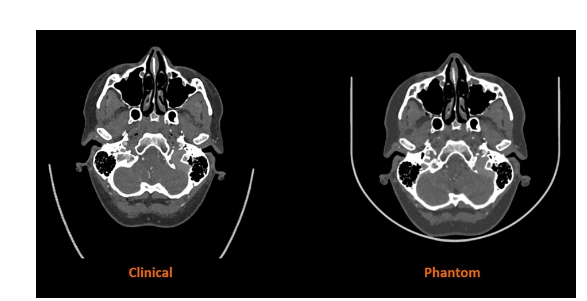

Stratasys與西門子醫(yī)療合作的早期研究結(jié)果表明,RadioMatrix人體模型能夠以極高的精度在CT成像中復(fù)制人體組織,即使在灰質(zhì)和靜脈等敏感區(qū)域,偏差也僅為1個(gè)亨氏單位(HU)。結(jié)合Stratasys的數(shù)字解剖技術(shù)和先進(jìn)的成像算法,最終生成的模型既保留了解剖和病理細(xì)節(jié),又為基于尸體的培訓(xùn)提供了一種一致且符合倫理的替代方案。預(yù)計(jì)這些模型將幫助放射科醫(yī)生改進(jìn)和驗(yàn)證CT掃描方案,同時(shí)加快高級成像算法的創(chuàng)建,從而實(shí)現(xiàn)更準(zhǔn)確的診斷和治療計(jì)劃。

△人體CT掃描與Stratasys公司3D打印模型CT掃描對比。圖片來自Stratasys公司。